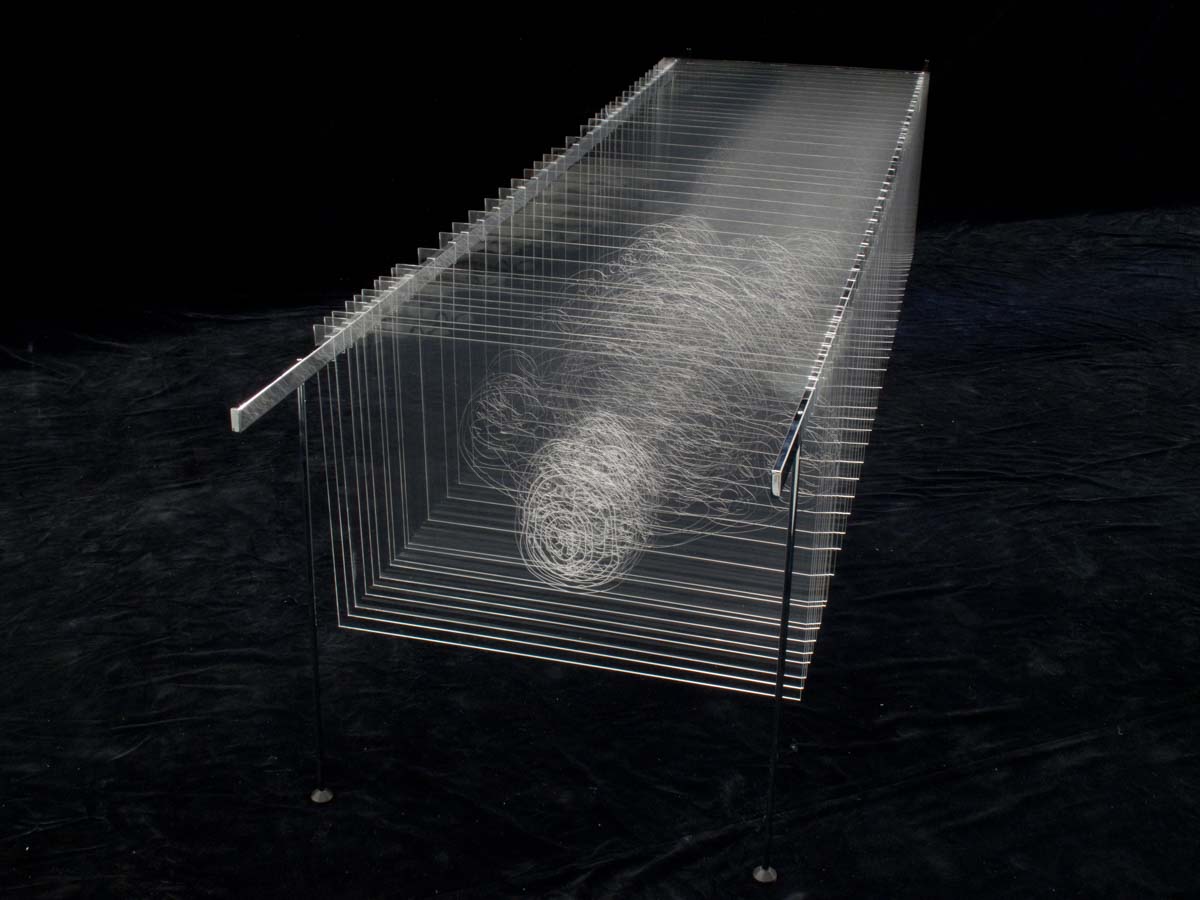

Découpe et gravure laser sur plexiglas, acier chromé 94 x 82 x 228 cm

41 coupes ont été sélectionnées et dessinées pour reformer le corps de Joseph Paul Jernigan, exécuté par injection au Texas en 1993. Ayant légué son corps à la science, il a été sectionné en 1878 tranches de 1 mm puis entièrement numérisé, ce qui a permis la création en 1994 du Visible Human Project, premier corps humain virtuel.